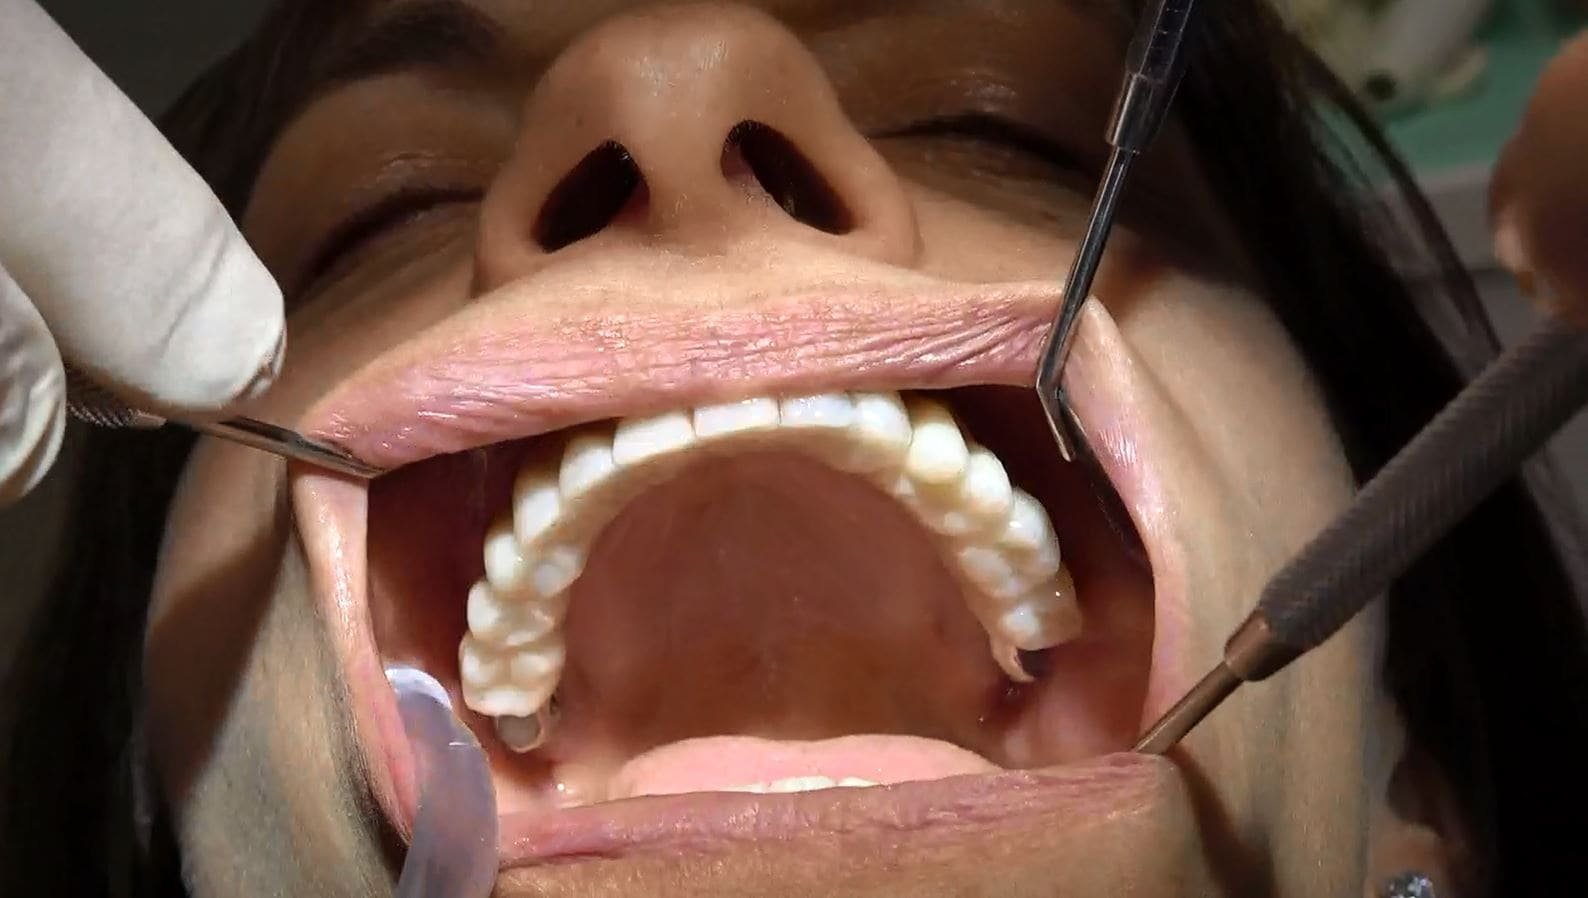

Segue cambio protesi da fissa provvisoria a fissa definitiva solo sotto, la parte superiore deve essere ancora sostituita con la protesi definitiva.

Secondo caso clinico paziente della Sardegna 30 anni di dentiera e in un ora e trenta passa da 30 anni di protesi mobile a dentatura fissa a carico immediato. Segue il momento del cambio protesi dopo 6 mesi da fissa provvisoria a fissa definitiva circolare 14 denti ceramica zirconio con una bellissima estetica per la piena soddisfazione della nostra paziente.

Dopo circa 6 mesi, una volta completata la fase di guarigione, viene realizzata e posizionata una protesi definitiva. Questa protesi può includere anche impianti pterigoidei per una maggiore stabilità e supporto. La protesi definitiva permette al paziente di avere un sorriso completo e funzionale, ripristinando la sua capacità di masticare e parlare correttamente.